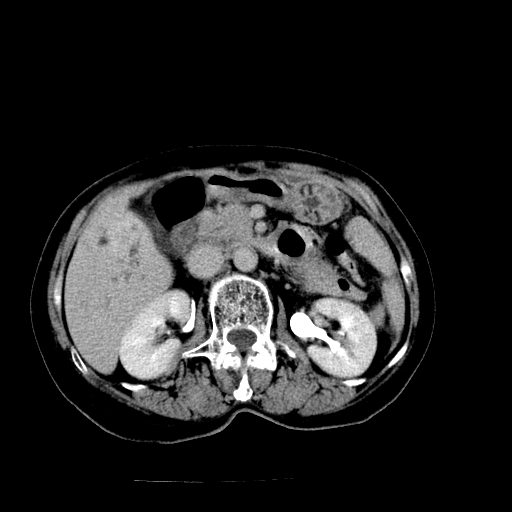

以下是引用卜一在2009-4-7 5:06:00的发言:[br]左右肝内胆管结石伴扩张合并胆系感染;不除外胆管细胞癌可能。支持! [br] [br]

以下是引用随光逐影在2009-4-7 8:21:00的发言:[br]肝内外胆管多发性结石并肝内外胆管扩张;胆系感染。